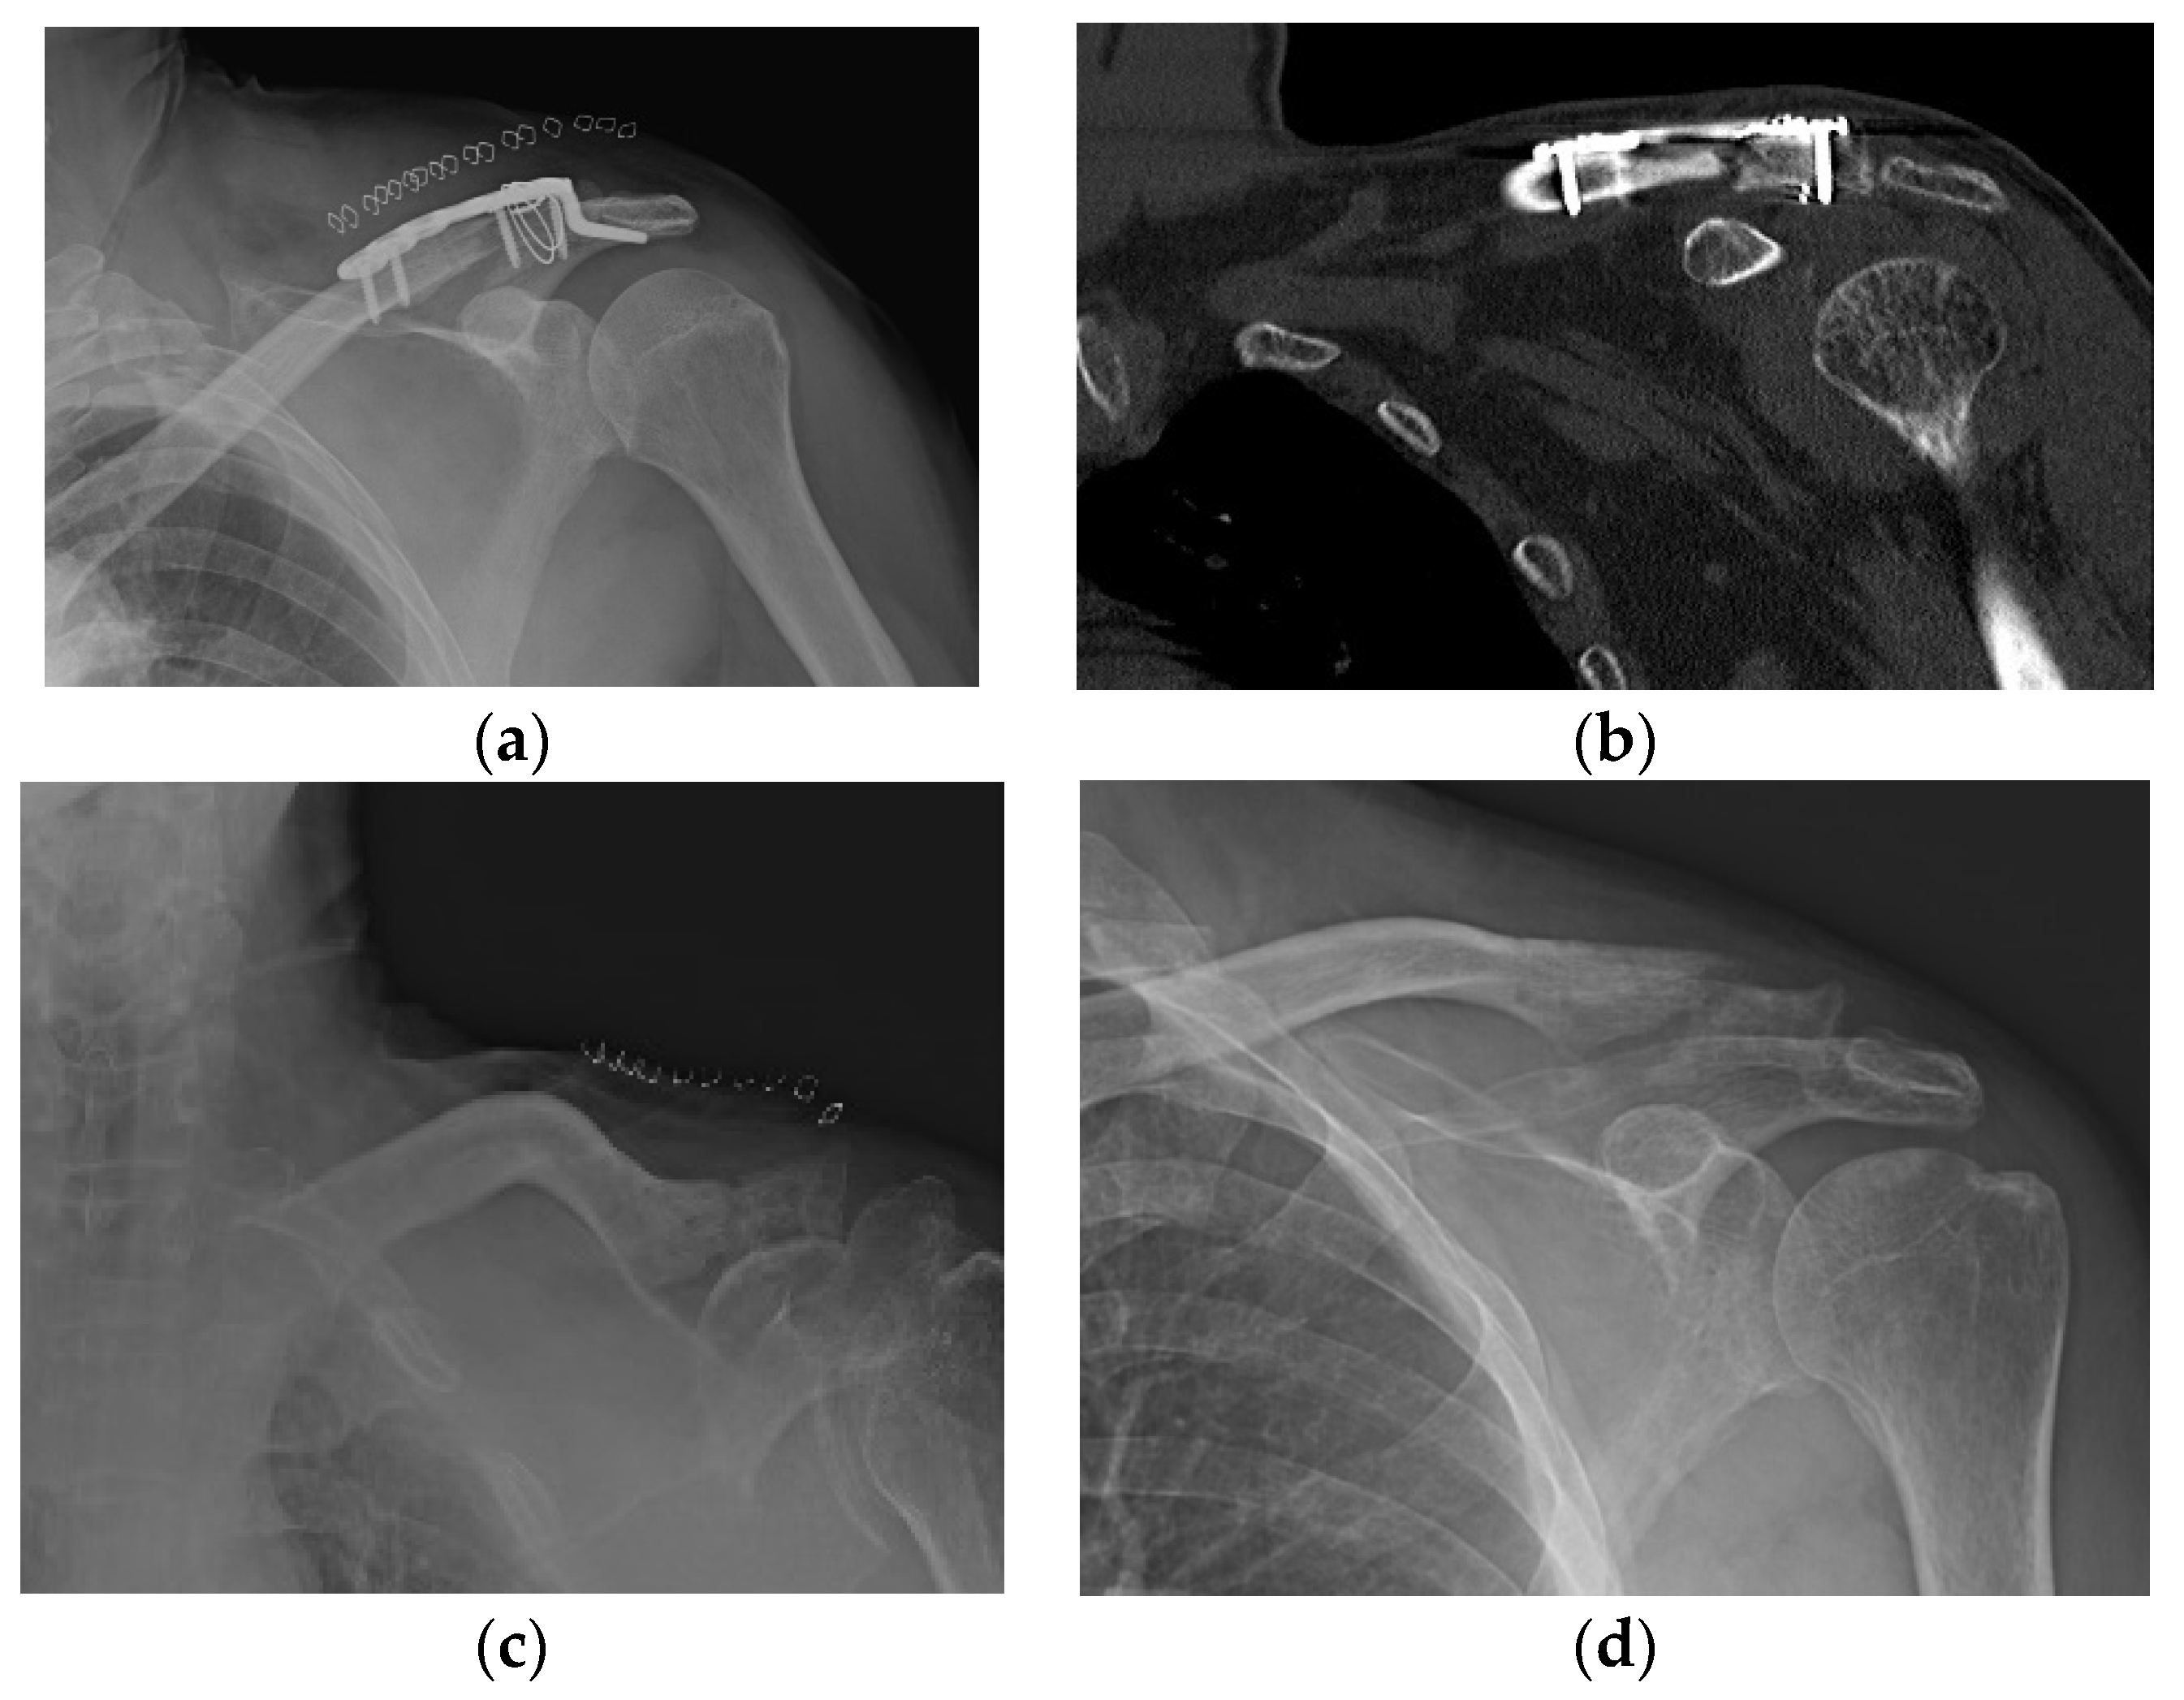

Figure 5. Peri-implant fracture. A 76-year-old female patient who underwent AO-type hook plating in the DCF group. (a) Postoperative clavicle anteroposterior radiograph view. (b) Patient showing peri-implant fracture on midshaft area of clavicle during the follow-up period of 4 months. (c) After removing the hook plate during the follow-up period, bone union is achieved.

Varying degrees of subacromial erosion occurred in all patients, and acromial fracture occurred in one case in the DCF group and seven cases in the ACD group (Figure 2 and Figure 3). Five (6.7%) cases showed incomplete union and one (1.3%) case showed peri-implant stress fracture in the DCF group (Figure 4 and Figure 5). Four of the five cases of incomplete union showed fracture union without additional surgery during the follow-up period, and one case did not heal at the final follow-up, although the patient did not show any discomfort with non-union (Figure 6). The peri-implant fracture healed with conservative management before plate removal. LOR was observed in nine patients with ACD. Before removing the hook plate, LOR occurred in six patients with ACD. Among these six patients, five showed acromial fracture and one showed serious subacromial erosion (Figure 7). After removing the hook plate, LOR occurred in three patients during the follow-up period. However, none of these patients with LOR among patients with ACD showed tenderness on the acromioclavicular joint or pain during the follow-up period. Regarding acromial fracture, one (1.3%, 1 of 36) case was observed in the DCF group and seven (8.3%, 7 of 33) cases were noted in the ACD group (Figure 4). There was no difference in the incidence of acromial fracture between patients with DCF and ACD (p = 0.066). All eight patients had fracture union without additional surgical treatment during the follow-up period.